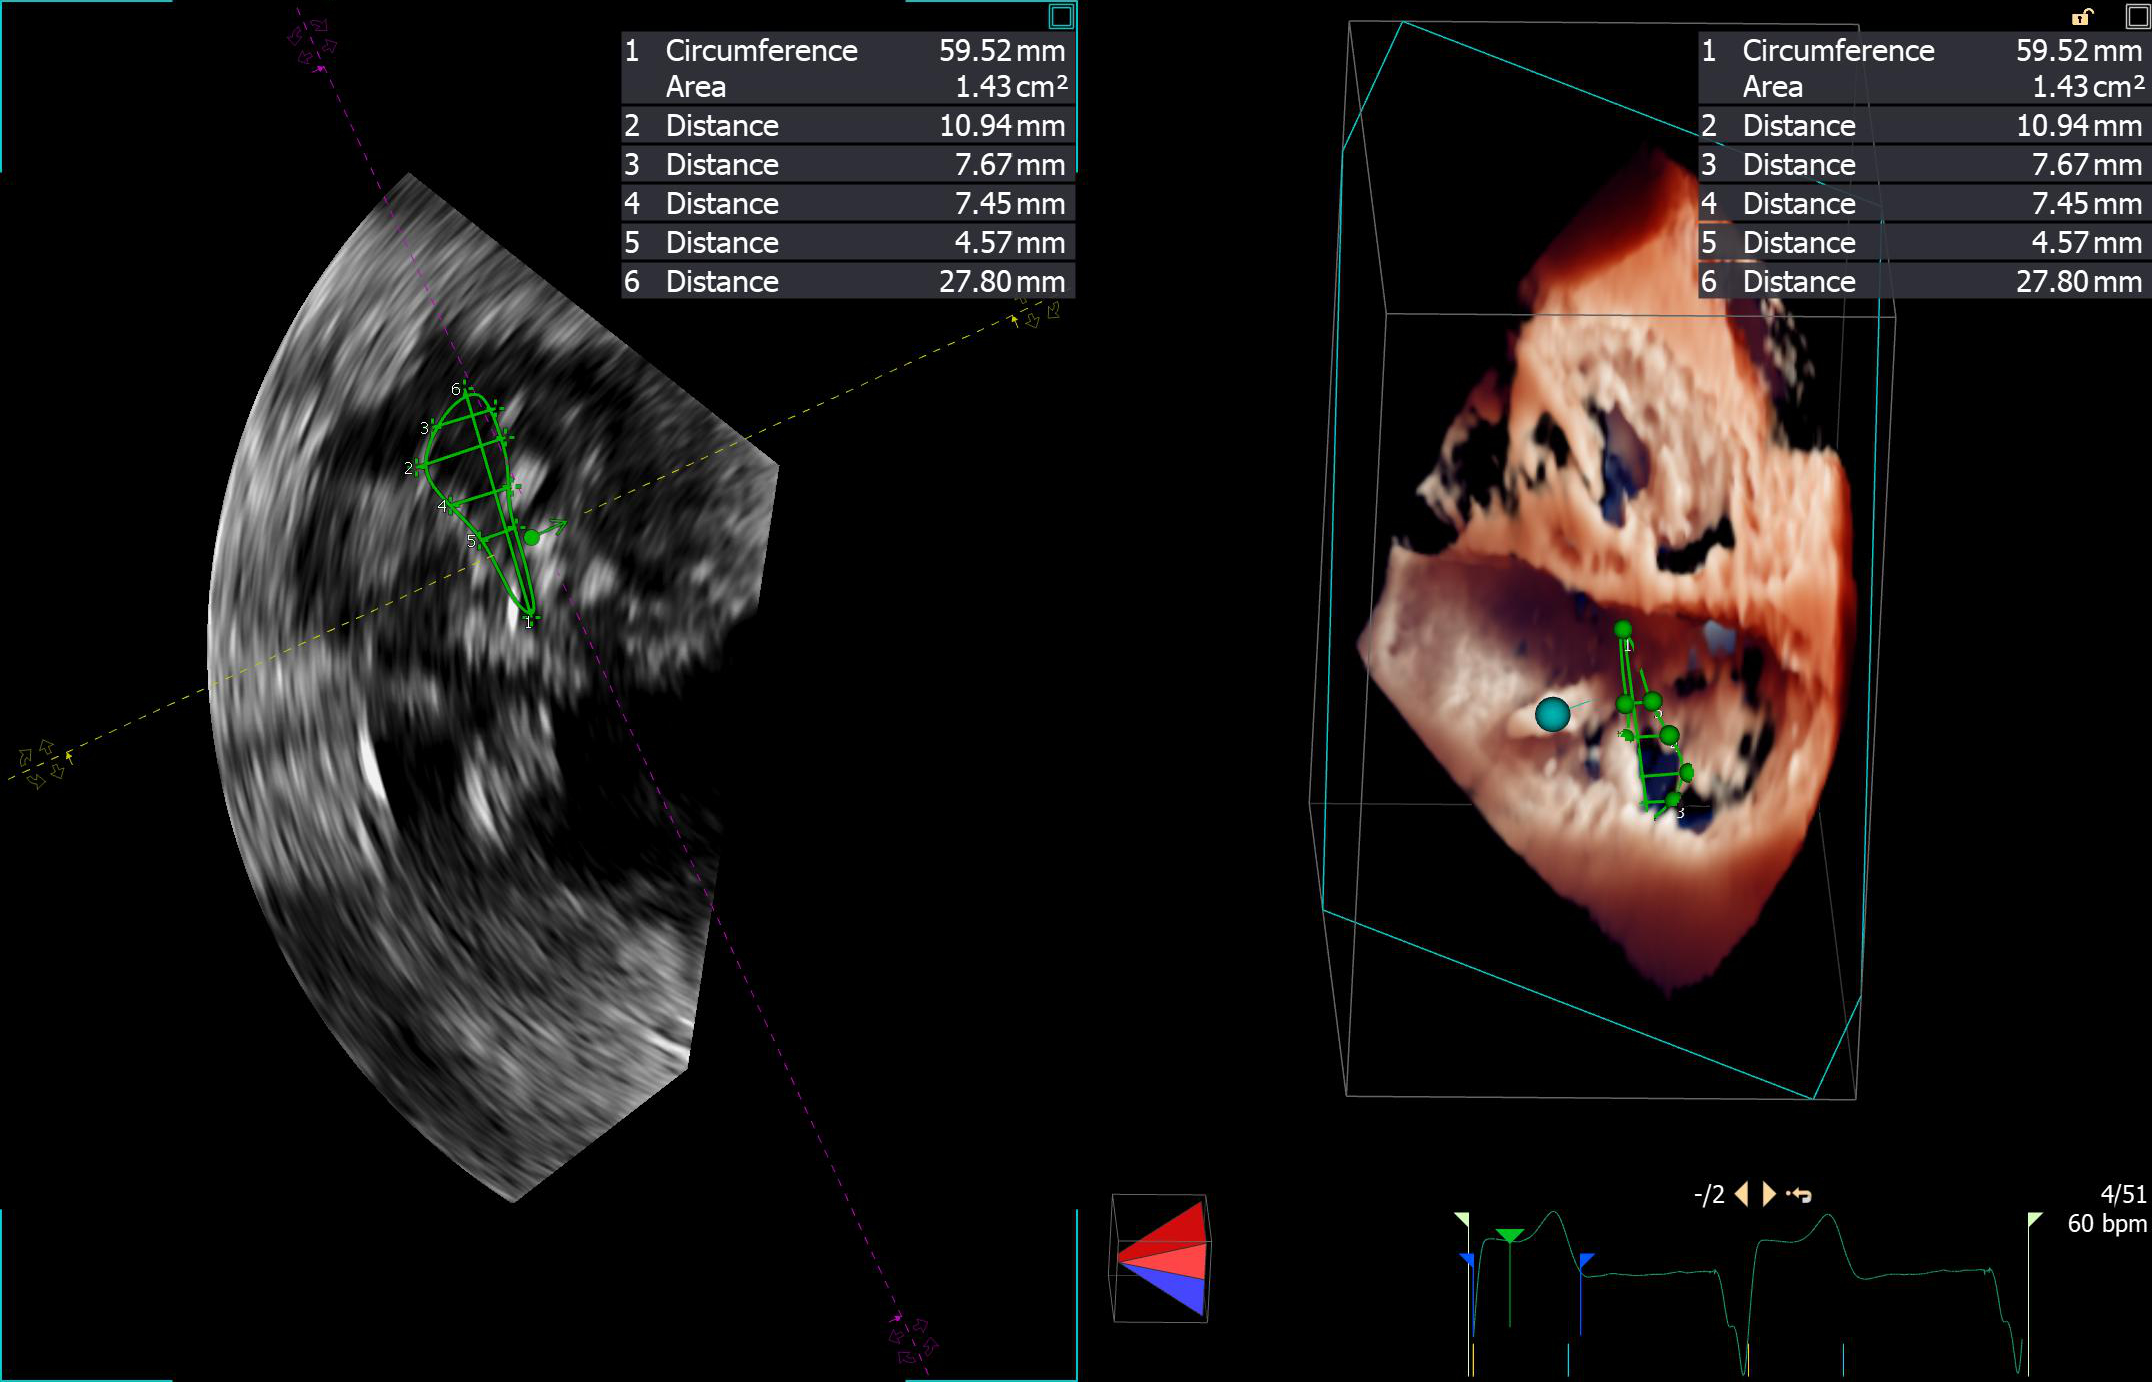

„Jak dotąd najczęściej stosowaną przez nas formą terapii był zabieg polegający na wprowadzeniu przez nakłucie żyły udowej specjalnych zapinek umożliwiających połączenie płatków, co poprawia ich przyleganie i zwiększa szczelność zastawki. Zabiegi tego typu, określane mianem przezcewnikowej naprawy metodą brzeg-do-brzegu (ang. transcatheter edge-to-edge repair – TEER), wykonuje się na bijącym sercu pod kontrolą dwuwymiarowej i trójwymiarowej echokardiografii w czasie rzeczywistym (tzw. echonawigacja). Niestety, ze względu na niekorzystną anatomię nie wszystkie zastawki można skutecznie naprawić tą metodą. W przypadku zbyt dużego poszerzenia wymiarów zastawki i oddalenia od siebie jej płatków zastosowanie klipsów może nie przynieść spodziewanego efektu; dla takich chorych rozwiązaniem mogłaby być całkowita wymiana zastawki” – tłumaczą specjaliści.

Od długiego czasu trwały intensywne badania nad opracowaniem protez zastawkowych, które można byłoby wszczepić bez konieczności przeprowadzania operacji kardiochirurgicznej, zastępując tym samym uszkodzoną zastawkę trójdzielną. Pierwsza tego typu zastawka – EVOQUE (Edwards Liefesciences, Irvine, USA) została zarejestrowana w Europie pod koniec 2023 r. Zbudowana jest ona z płatków wszytych w samorozprężalną ramkę, która jednocześnie stanowi element mocujący zastawkę w sercu. Przed wszczepieniem całość zamocowana jest na sterowalnym systemie doprowadzającym, który umożliwia przeprowadzenie zabiegu z dostępu przez żyłę udową. Procedura wykonywany jest głównie pod kontrolą echokardiografii trójwymiarowej w czasie rzeczywistym (echonawigacja).

Od 2021 r. pracujemy już z systemami zaprojektowanymi specjalnie do naprawy niedomykalności trójdzielnej, które charakteryzują się większą precyzją i skutecznością. Mimo to duża część chorych nie spełnia kryteriów anatomicznych do założenia „klipsa”: pierścień zastawki jest zbyt poszerzony, a płatki leżą zbyt daleko od siebie, by dało się je zbliżyć i skutecznie uszczelnić zastawkę. Dla tej grupy przełomem stało się wszczepienie samorozprężalnej protezy EVOQUE drogą przezżylną. Dostępna w Europie od niespełna dwóch lat zastawka jest pozycjonowana pod kontrolą echokardiografii przezprzełykowej bez otwierania klatki piersiowej. Wypełnia lukę w tej dużej grupie chorych kierowanych do zabiegów naprawczych. Za jej pomocą będziemy w stanie leczyć pacjentów, którzy są objawowi, nie mają jeszcze zaawansowanych cech niewydolności prawokomorowej, ale z drugiej strony też już mają na tyle zaawansowaną wadę, że nie można jej naprawić za pomocą dotychczasowych metod przeskórnych.

Dr hab. n. med. Piotr Scisło, kardiolog zajmujący się echokardiografią, WUM:

Chronologicznie najpóźniej terapie przezcewnikowe znalazły zastosowanie w leczeniu niedomykalności trójdzielnej. Powodem była skomplikowana anatomia i obrazowanie zastawki trójdzielnej. Przełomem dla Polski stał się rok 2018, kiedy to zespół WUM wykonał pierwszą w kraju przezcewnikową naprawę zastawki trójdzielnej metodą brzeg-do-brzegu.

Ograniczenia anatomiczne sprawiają, że nie każdy chory jest jednak dobrym kandydatem do leczenia niedomykalności metodą brzeg-do-brzegu, potrzebna jest wymiana zastawki, a nie jej naprawa. Odpowiedzią na tę lukę stała się zastawka EVOQUE – pierwsza bioproteza do przezcewnikowej implantacji w ujście trójdzielne, która została dopuszczona do użytku w Unii Europejskiej w październiku 2023 roku.